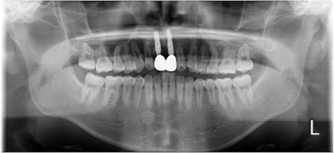

20代 男性

治療前

治療後

治療後- リスク・副作用

(薬・注射・レントゲン・CT・データ分析・骨造成・サージカルステント・血液検査・仮歯) - 年齢/性別

- 20代/男性

- 患者の具体的な症状

- 1年前に左上12 右上1の根の治療をし、その後放置していたら、左上2が破折した。

左上2インプラント補綴 左上1右上1オールセラミック装着。

歯根破折と虫歯による痛み、審美障害を主訴として来院。 - 検査方法

- コーンビームCT、レントゲン撮影

- 診断結果

- 左上2 歯根破折

- 治療詳細

- 左上抜歯後、インプラント埋入1本

骨造成あり 局所麻酔

インプラント治療後、左上1右上1セラミック修復2本 - 通院回数

- 9回

- 治療期間

- 12か月